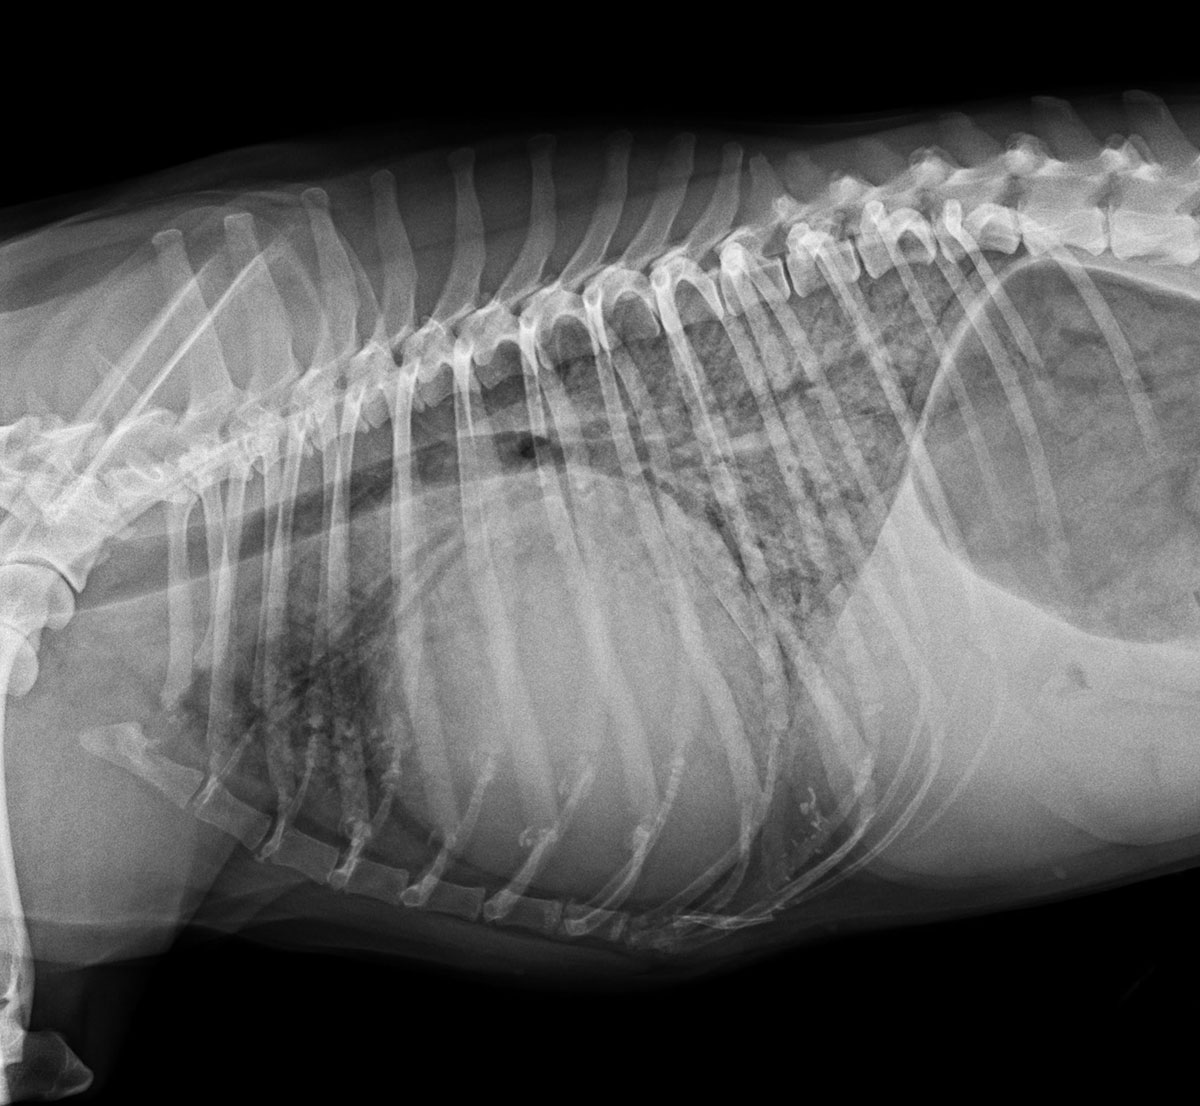

Chirurgie tissus mous thoraciques